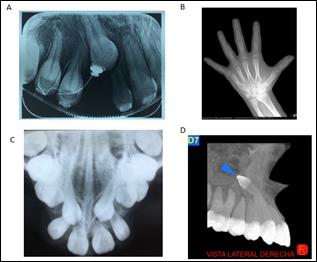

Otras radiografías complementarias que tenemos a disposición son la radiografía oclusal, principalmente para la ubicación de piezas incluidas, y valoración de la sutura media palatina; la radiografía periapical, que permite valorar piezas incluidas, avances en el tratamiento de ortodoncia y medición de piezas dentales (15); la radiografía de ATM boca abierta, boca cerrada, sobre todo cuando hay antecedentes de dolor o ruidos en la misma; la radiografía carpal para la valoración de la maduración esqueletal del paciente (16); y actualmente contamos con la tomografía dental, que transformó completamente el diagnóstico, permitiendo una visión en tres dimensiones (17).

Fig. 5. Estudios complementarios. a) Rx periapical b) Rx carpal c) Rx oclusal d) Tomografía dental. Cortesía Esp. Byron Villarreal.